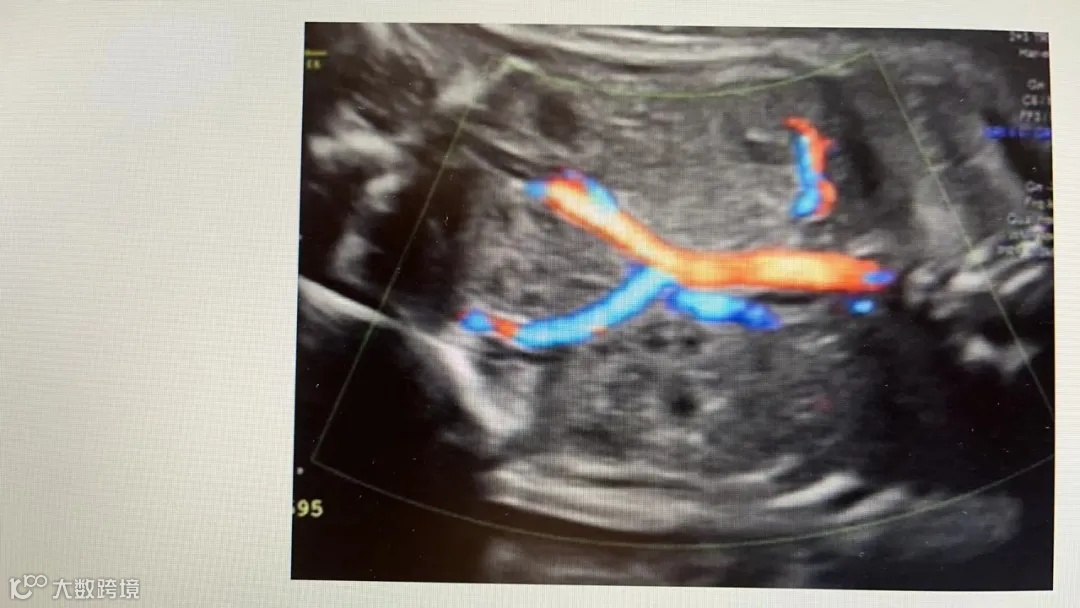

盆腔异位肾